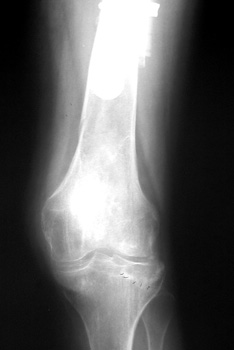

Insufficiency fracture lateral tibial plateau in patient with long revised left femoral stem

STRESS REACTION

Stress reaction secondary to altered biomechanics. Cortical thickening is present medial to the femoral component tip.